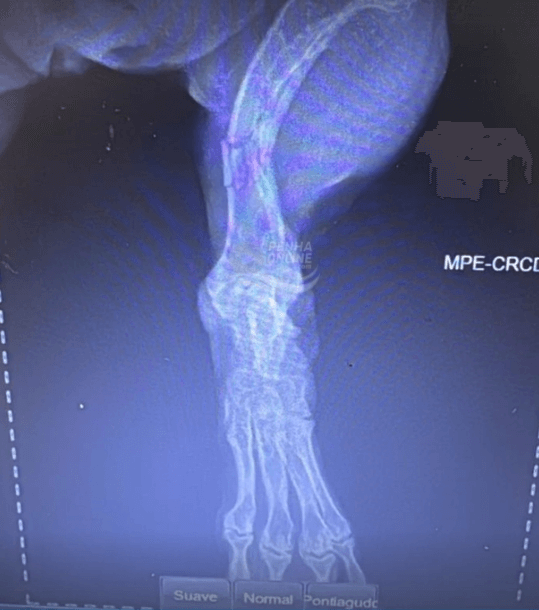

Uma tutora denunciou um ataque sofrido por sua cadela na Praia da Armação, em Penha, e pede ajuda para identificar os responsáveis pelos animais envolvidos. O caso ocorreu no dia 26 de dezembro e resultou em ferimentos graves no animal, que precisou passar por cirurgia.

“Queria relatar um ocorrido com nossa cachorrinha na Praia da Armação. Estávamos com ela na praia e, ao ir embora, uns cachorros da raça poodle escaparam da guia e a atacaram, quebrando a pata dela. Minha cachorra é uma salsichinha pequena, super dócil. Os rapazes que estavam com os cachorros eram dois, com cinco poodles. Temos casa em Penha há mais de 30 anos e frequentamos a praia, isso nunca aconteceu e nunca tínhamos visto algo assim. Queria expor aqui a nossa história para ver se alguém que viu conhece os rapazes, pois nossa pequena Cacau precisou de cirurgia e tivemos vários gastos por causa da irresponsabilidade deles. Primeiro, por que levar tantos cachorros ao mesmo tempo se não conseguem cuidar? Segundo, já imaginou se atacam uma criança ou uma pessoa idosa? Fica aqui minha indignação. Temos imagens da cachorrinha machucada e laudo da clínica veterinária que atendeu ela”, relatou a tutora ao Penha Online.